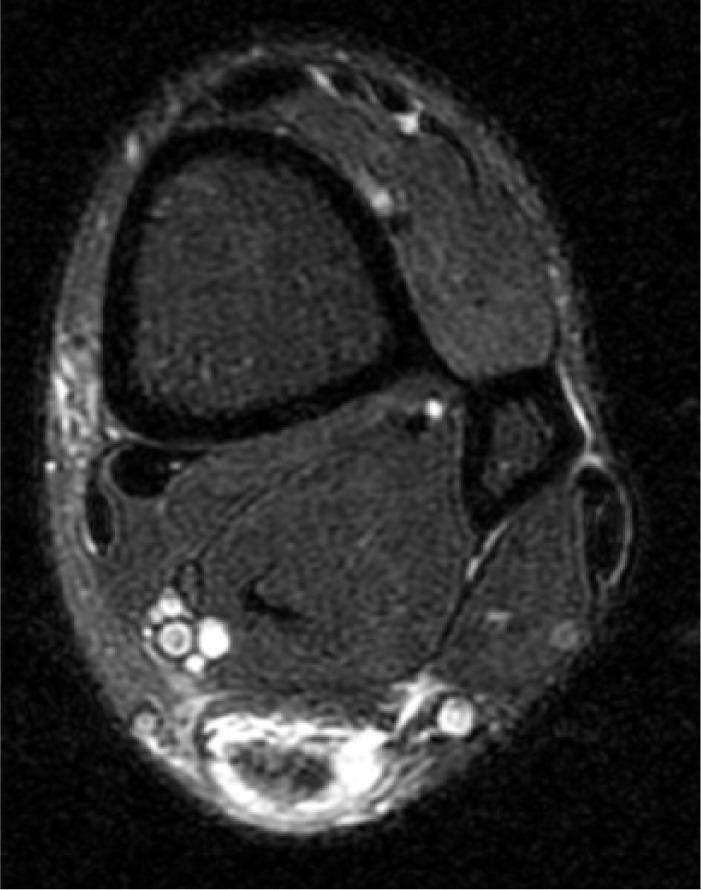

We reviewed and analysed this patient's records containing the sport-specific anamnesis, pre-existing condition, anamnesis of medications and therapy. The three injuries were magnetic resonance imaging-proven. Furthermore, the tendon's condition was examined histologically in the context of the operative treatment through lace technique of the Achilles tendon and transfer of the peroneus brevis to the peroneus longus. We also researched the literature for bilateral ruptures of the peroneal tendons.

我们回顾并分析了该患者的记录,包括运动专项病史、既往病史、用药史和治疗情况。这三处损伤均经磁共振成像证实。此外,在通过跟腱编织技术和将腓骨短肌转移至腓骨长肌进行手术治疗的过程中,对肌腱状况进行了组织学检查。我们还在文献中搜索了腓骨肌腱双侧断裂的病例。